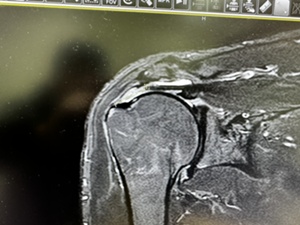

右肩の棘上筋の断裂が見つかり 博多メディカルクリニックの田中Drに手術をしてもらうことに

右肩の棘上筋が約2㎝断裂している様で手術を受けます。